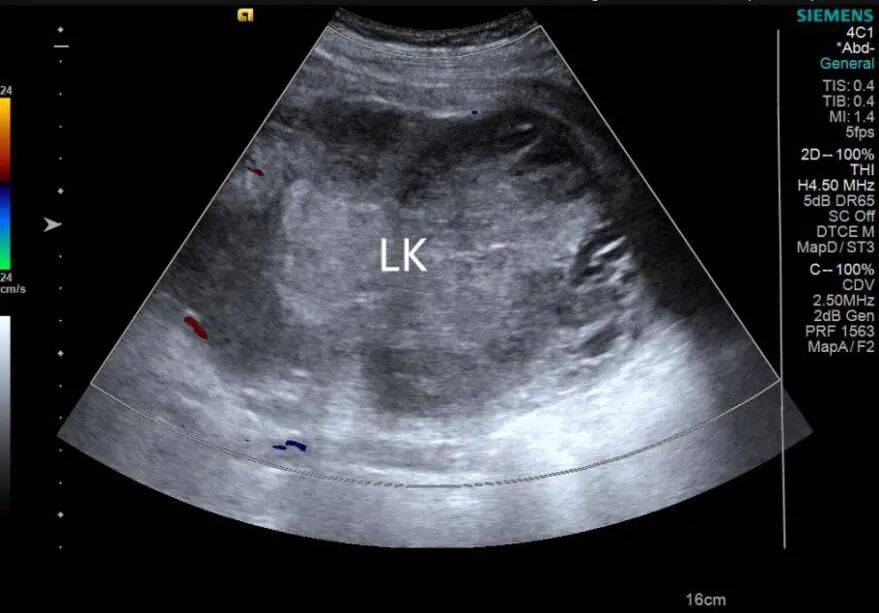

1. 左肾形态失常,体积增大,内部结构紊乱,呈混合性回声,以实性为主,内部可见不规则无回声。CDFI:混合性回声内部及周边未见明显血流信号(图 1、2)。

图 2 彩色多普勒超声示内部未见血流信号( LK 左肾)